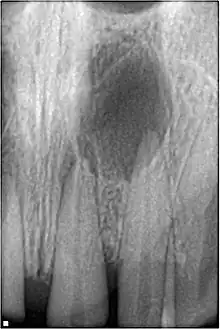

| A broken upper front tooth. The layers of tissue that make up the tooth are clearly visible, with the pink pulp standing out against the paler dentine and tooth enamel. | |